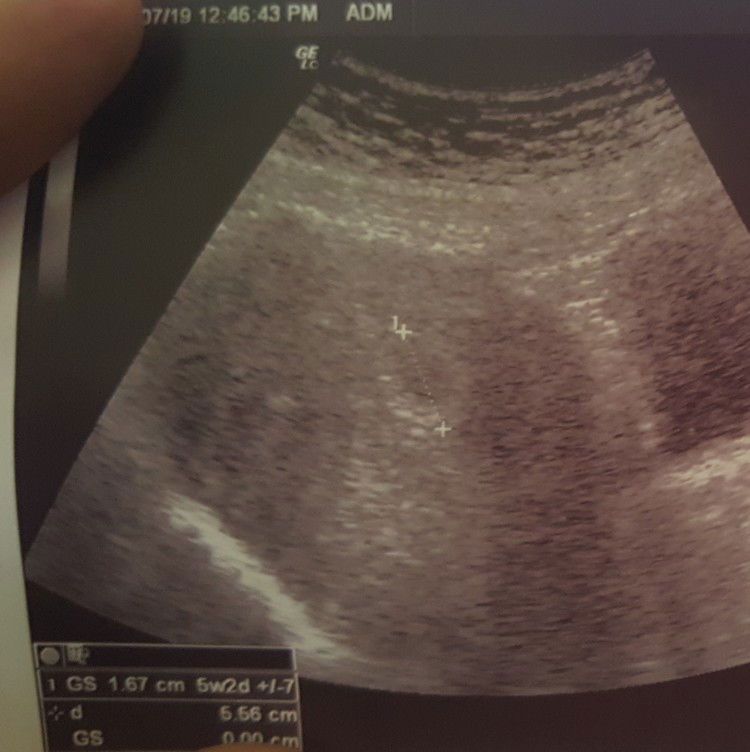

Siapa pernah mcm saya? Doc kata kantung tak cantik. Tapi alhamdulillah. Yg ni scan size kantung sama dgn tarikh. 5w Patot scan fibroid kat Hosp haritu. Tapi jadi focus ke pregnancy.. Pernah gugur bulan 3, masa 8 mggu.. Doc tanya, tak merancang ke? Sengih je la.. so kene scan lagi skali lagi 2 minggu. Risaunya hati..